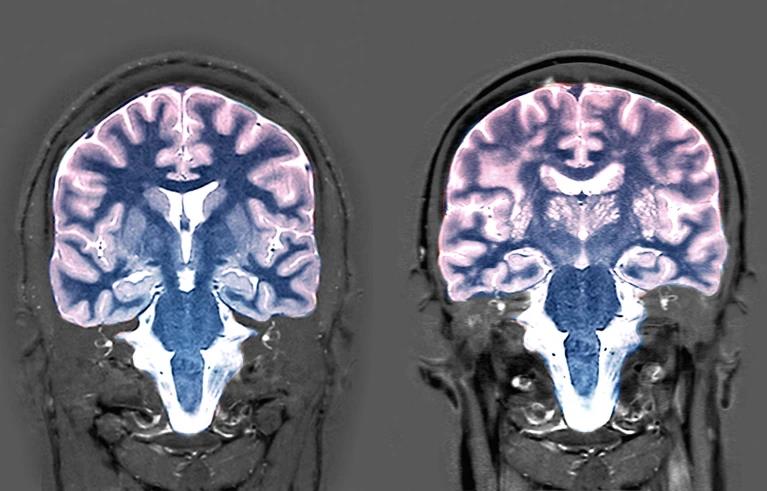

연구진은 기계 학습을 사용하여 1만 949명의 뇌 영상 데이터를 분석해 뇌의 부피, 표면적, 백질 분포와 같은 특징을 기반으로 사람의 뇌 연령을 계산하는 모델을 만들었다.

연구진은 그 과정에서 뇌 연령 차이(뇌 연령과 실제 연령의 차이)와 관련된 단백질을 식별하고자 했다. 이를 위해 연구진은 4696명의 혈액 샘플에서 2922개의 단백질 수치를 분석하고 스캔에서 얻은 동일인의 뇌 연령과 비교했다. 참여한 그룹의 절반 이상이 여성이었다.